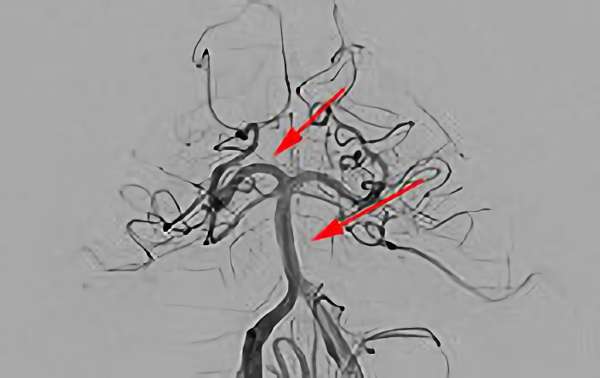

No.1583 手術前

No.1583 手術中

No.1583 手術後